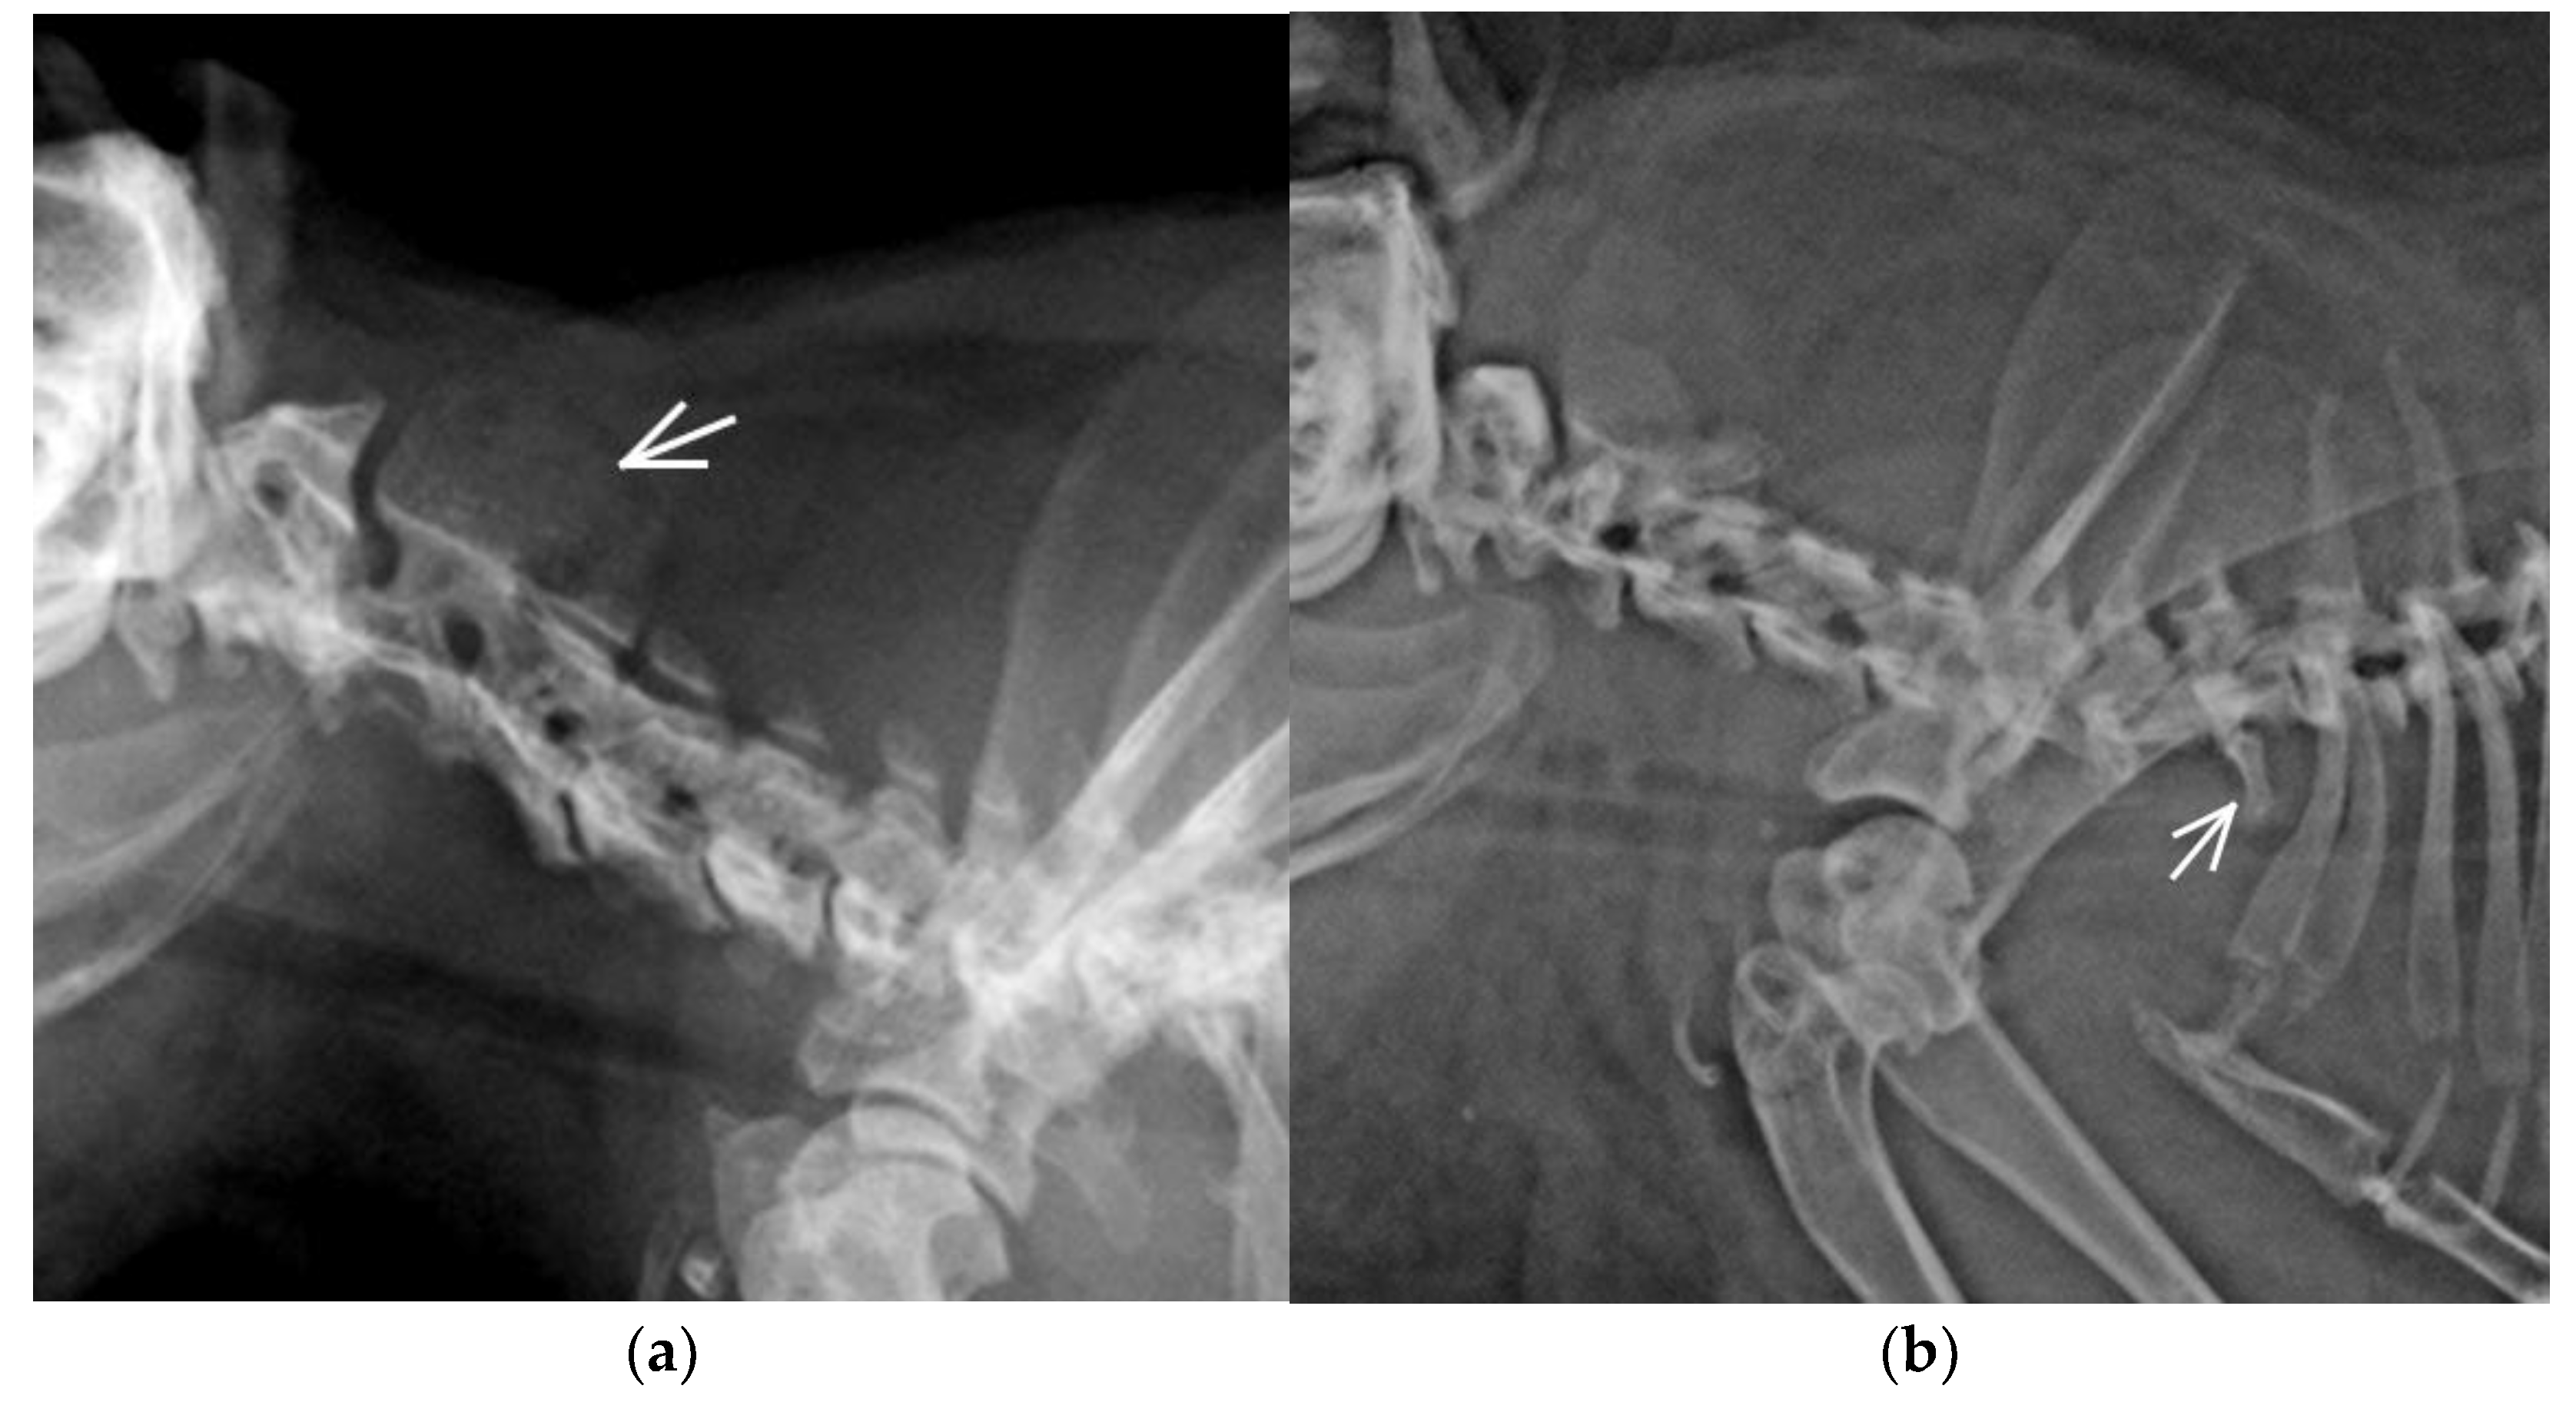

| LTV | Asymmetrical | LS junction | C7/Th13/L5+LTV/S4/Cd6 | 1 | 2.08 | 16.67 | F |

| LS junction | C7/Th13/L5+LTV/S3/Cd6 | 1 | M | ||||

| LS junction | C7/Th13/L5+LTV/S4/Cd5 | 1 | F | ||||

| LS junction | C7/Th13/L5+LTV/S4/Cd6 | 1 | F | ||||

| LS junction | C7/Th13/L6+LTV/S3/Cd5 | 1 | M | ||||